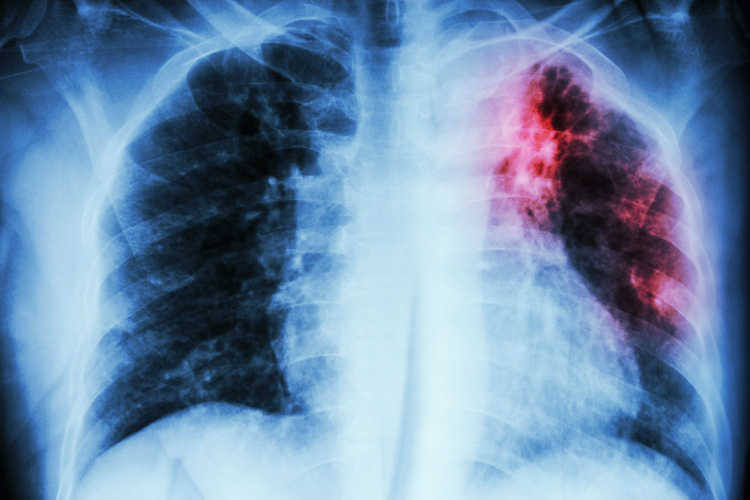

image

Если говорить о самом распространенном виде болезни, туберкулезе легких, первые признаки заболевания напоминают острую респираторную инфекцию. Длительное время болезнь может проходить бессимптомно. В запущенных случаях туберкулез может привести к менингиту, к необходимости удаления легкого или другого органа, и даже к летальному исходу.

Больной туберкулезом кашляет часто и регулярно. На начальном этапе кашель сухой и приступообразный. По мере развития болезни кашель становится влажным, начинает выделяться мокрота. Кашель, продолжающийся несколько недель, не связанный с простудой или бронхитом, является верным признаком туберкулеза.

7. Кровохарканье

Появление крови при откашливании говорит о том, что болезнь приобретает инфильтративную форму. Вместе с тем, кровохарканье является симптомом и других опасных болезней, оно может говорить о злокачественных опухолях в легких, об острой сердечной недостаточности. В любом случае, такой симптом требует немедленного обращения за медицинской помощью. Только специалист способен установить истинную причину проблем.

При наличии положительного ответа на реакцию Манту потребуется прохождение более детального обследования. Основным методом диагностики туберкулеза является флюорография (томография, рентгеноскопия). Также проводятся пробы мокроты, анализ крови, мочи. В специализированных медицинских учреждениях доступны такие информативные методы диагностики болезни как трансторакальная игловая биопсия, трахеобронхоскопия, бронхоскопический лаваж, торакоскопия (плевроскопия).